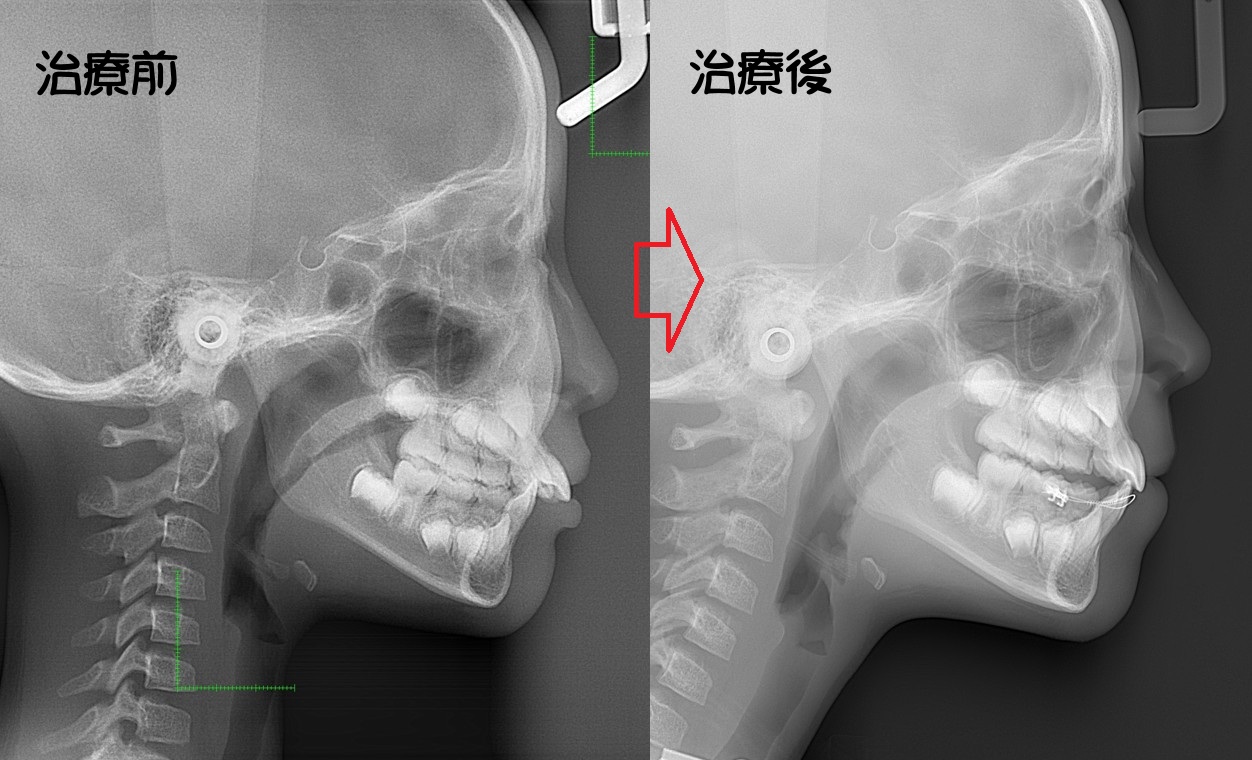

顎変形症

骨格性反対咬合・骨格性上顎前突・骨格性開咬・骨格性下顎側方偏位 などの外科矯正手術を必要とするもの

外見の改善を重要視するならば、矯正治療と外科処置を併用することにより適切な噛み合わせを回復したほうがよい場合もあります。

・主訴:下あごが出ている

・診断:骨格性下顎前突

・年齢:27歳

・使用した主な装置:マルチブラケット装置

・抜歯部位:なし

・治療期間:30か月

・通院回数:36回

・費用の目安:保険適応。保険矯正代金は、20万円くらい。症状・期間によってかわります。

・その他大学病院で外科矯正手術代金がかかります。